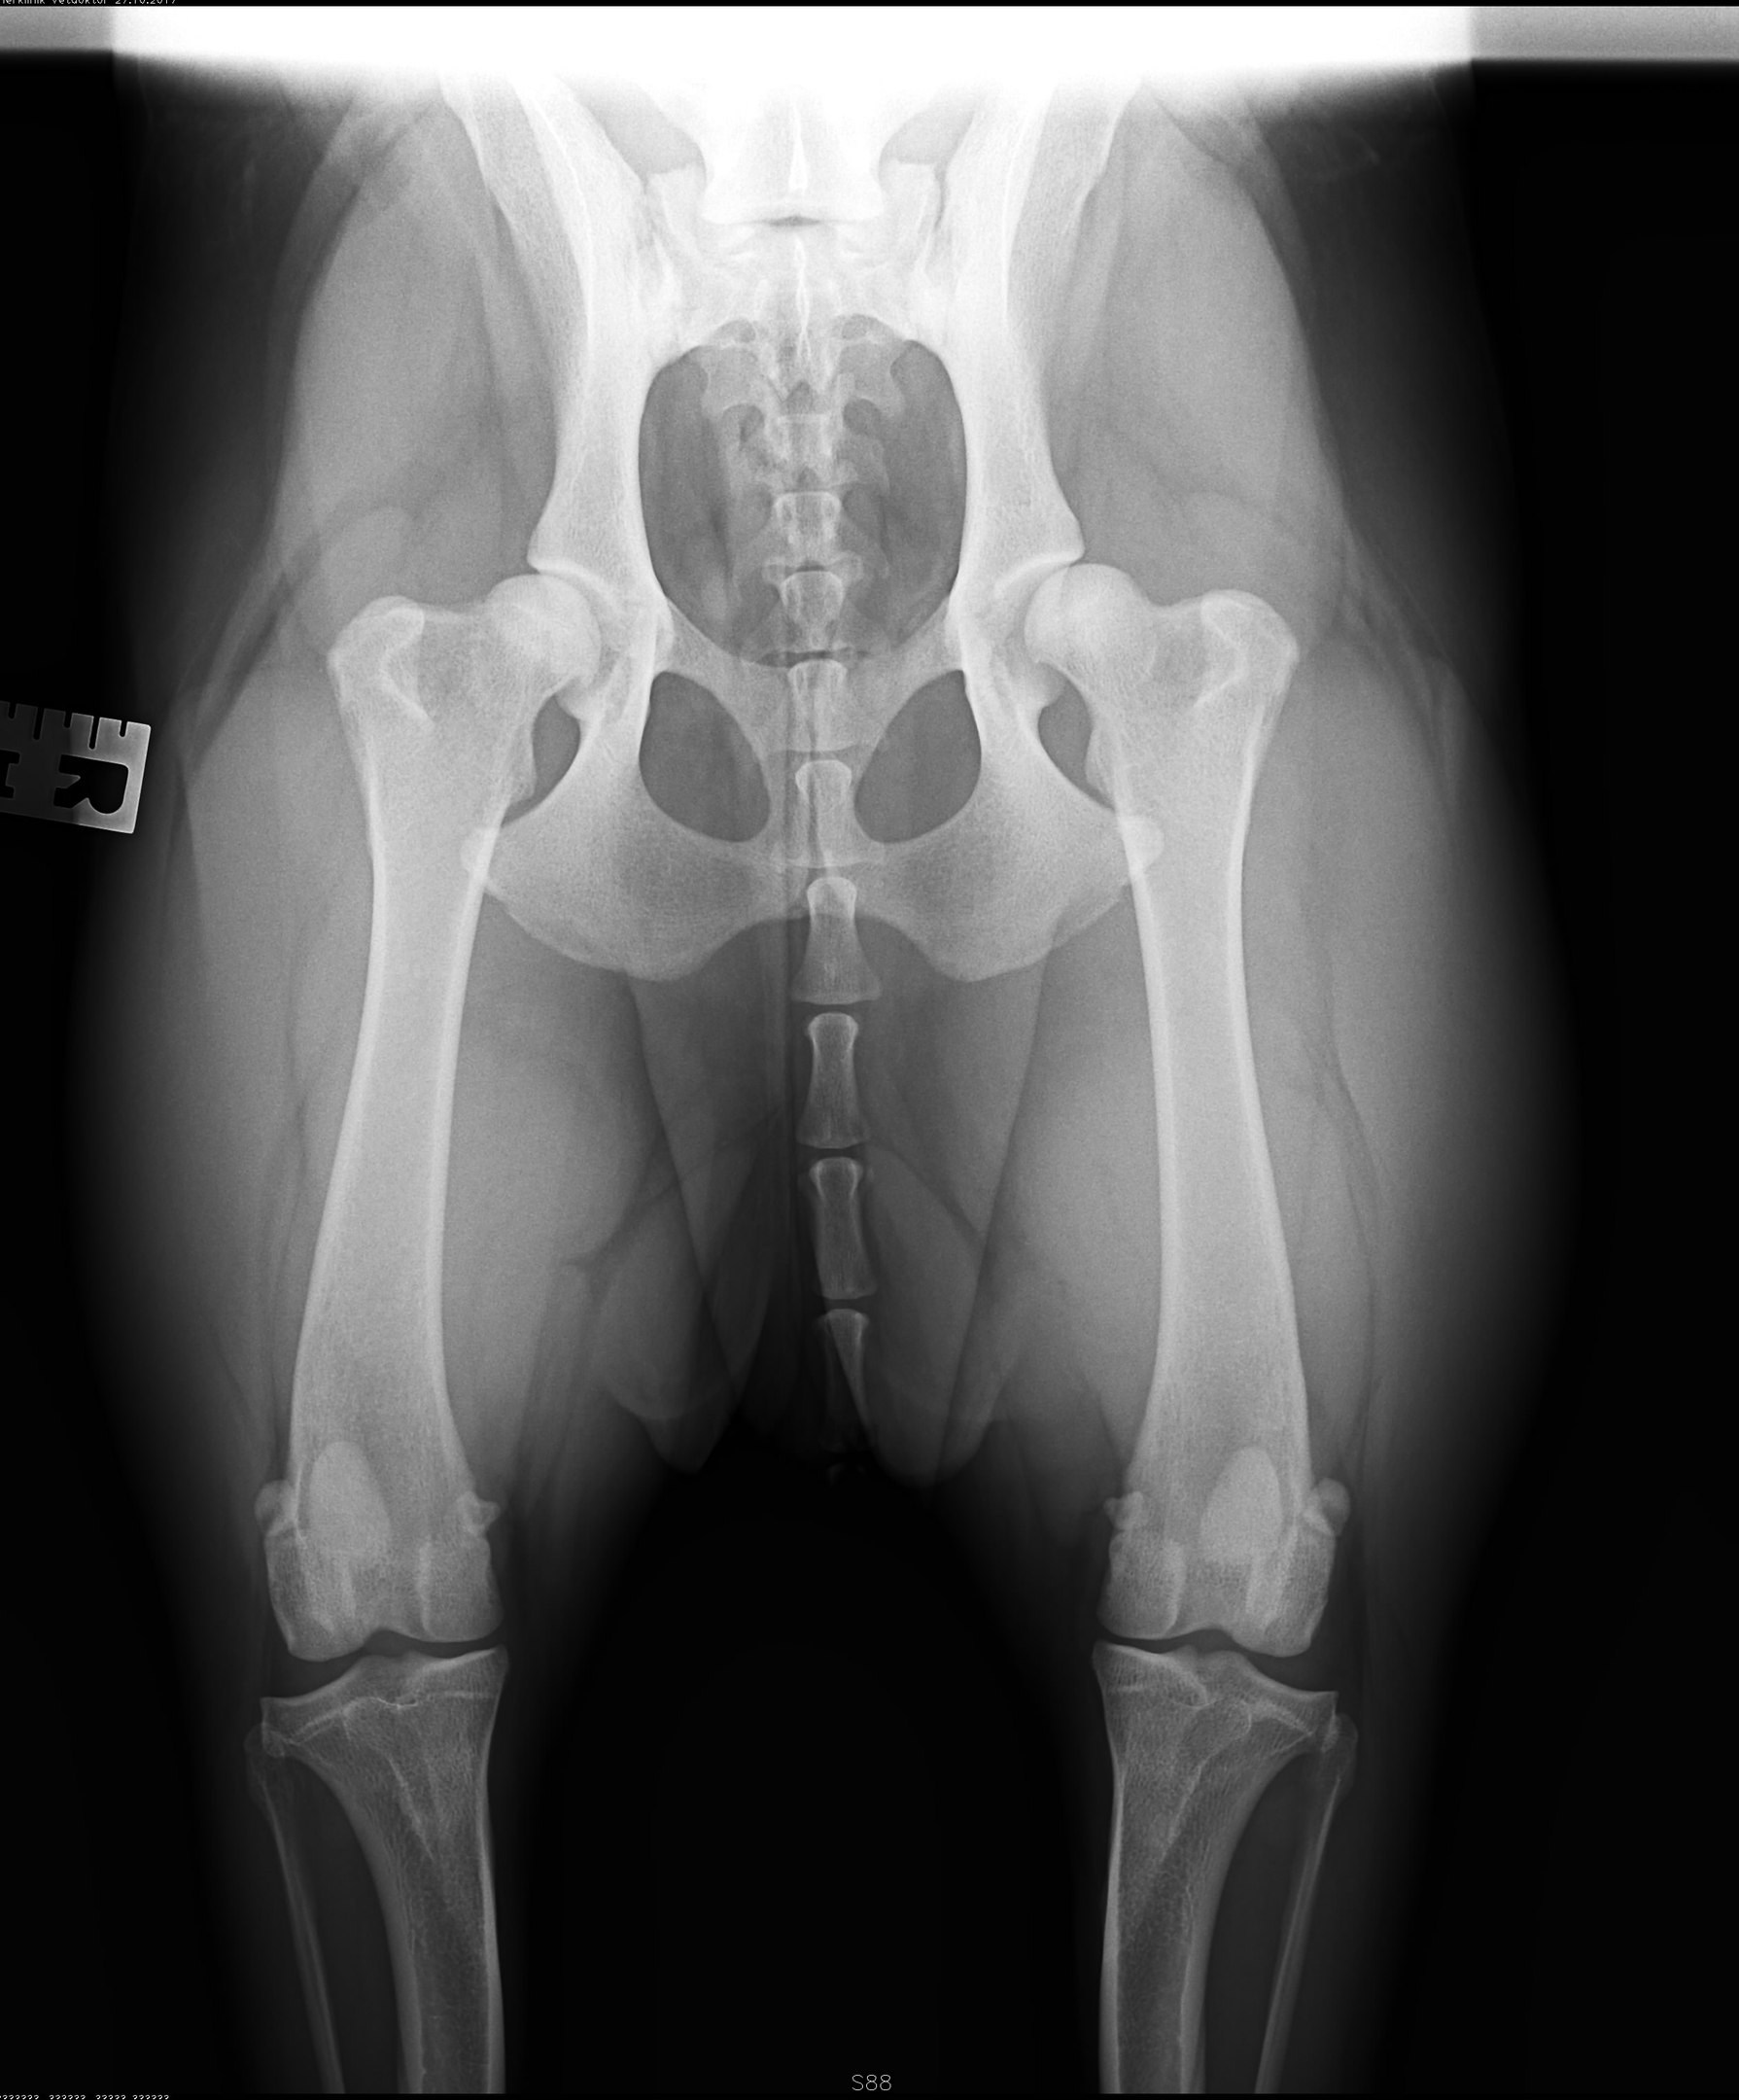

Рентген ТБС: Нормальные показатели

Раздел: Необычные решения